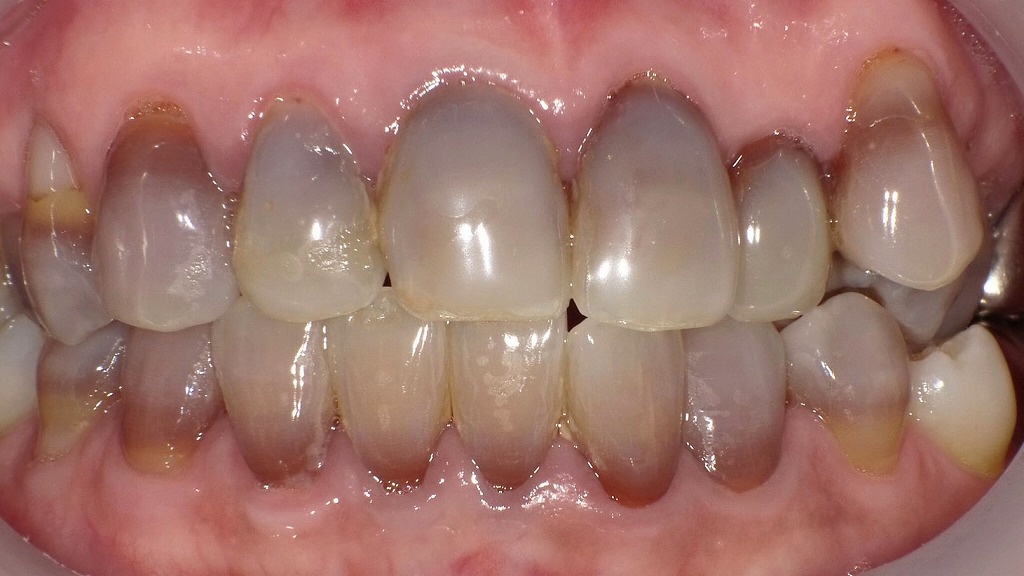

📷テトラサイクリン歯の症例

歯頸部が変色したテトラサイクリン歯

軽度の変色ですが歯頸部にあるためホワイトニングがやや難しいケースです。

歯の中央部に褐色ラインがあるテトラサイクリン歯

ホームホワイトニングでかなり綺麗になる可能性のある症例です。

重度のテトラサイクリン歯

全歯牙に渡って黒褐色の変色が起こっています。 ホワイトニングだけでは難しくラミネートベニヤの適応症例です。

前歯にテトラサイクリン歯は認められず

前歯の変色が見られないところを見ると8歳から9歳頃テトラサイクリンの服用をしたものと思われます。